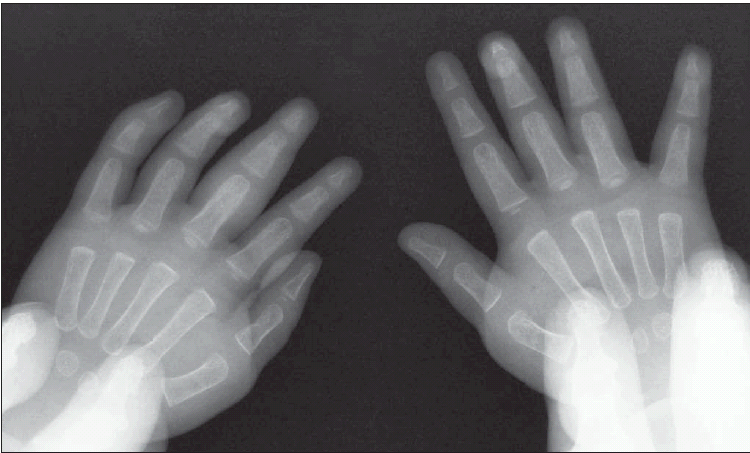

Radiograph of hands is shown.

ANSWER: JUVENILE IDIOPATHIC ARTHRITISThe radiograph showed soft tissue swelling at the distal aspect of the third phalangeal, distal interphalangeal, and proximal interphalangeal joints of the left hand (Figure). There were no bony abnormalities or joint-space widening. Radiographs of the left knee showed mild swelling and no fracture or dislocation. These findings suggested a diagnosis of juvenile idiopathic arthritis (JIA). The laboratory test results ruled out other possible causes of arthritis and arthralgia, including Lyme disease, systemic lupus erythematosus, and septic arthritis

On radiographic studies, the fingers are typically involved in monarticular or oligoarticular JIA, whereas the entire hand is affected in those with polyarticular JIA.6